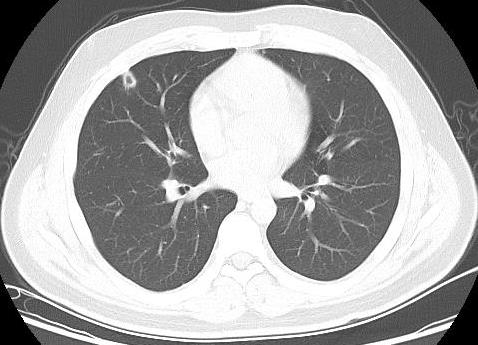

患者男性,21岁,主因“间断发热、寒战伴头晕头痛2周”于2021年11月18日急诊收入院。患者诉2周前进食烧烤后出现发热,体温最高可达42℃, 伴畏寒、寒战、咽痛、头晕、头痛、乏力,就诊于本院耳鼻喉科后,查体见扁桃体有脓点,快测降钙素原(procalcitonin,PCT)为37.27 ng/mL,胸部CT检查未见异常,考虑诊断为“急性化脓性扁桃体炎”,先后给予左氧氟沙星、阿奇霉素抗感染及甲泼尼龙控制炎症后上述症状未见明显好转,为进一步治疗,收入急诊病房治疗,既往体健,入院时查体:体温41℃,脉搏98次/min,呼吸频率23次/min,血压120/60 mmHg(1 mmHg=0.133 kPa),患者神志清楚,急性病容,精神较差,颈部浅表淋巴结触及肿大,右侧较大约2.0 cm ×0.5 cm,左侧较大约1.3 cm×0.7 cm,质软,活动度好,界限清楚,有压痛,表面皮肤无红肿,无破溃,双肺呼吸音清,未闻及干湿性啰音,心脏听诊无杂音,腹软,无压痛及反跳痛,双下肢无水肿。血常规检查白细胞计数10.49×109/L, 中性粒细胞百分比94.6%,血红蛋白120 g/L, 血小板计数107×109/L,PCT 42.83 ng/mL,白介素6(interleukin, IL-6)980.30 pg/mL,C反应蛋白211 mg/L,G试验、GM试验阴性。胸部CT检查示右肺上叶可见一单发实变影,其内可见空洞(图 1)。根据病史、查体和辅助检查考虑诊断为肺脓肿,给予注射用哌拉西林钠他唑巴坦4.5 g Q8h治疗,入院第2天,患者仍有发热,体温最高38.7℃,给予对症处理,入院第3天患者体温峰值有所下降,体温维持在37~38℃,考虑抗炎有效,痰培养结果回报为纹带棒杆菌,草绿色链球菌(奈瑟菌属),考虑这2种细菌为皮肤或口腔的正常菌群,为条件致病菌,该细菌导致发热的可能性较小,继续给予哌拉西林钠他唑巴坦治疗。入院第5天血培养回报血液中找到坏死梭杆菌,考虑为血流感染。加用甲硝唑1 g每8 h一次抗感染治疗,复查血常规白细胞计数8.14×109/L, 中性粒细胞百分比81.5%,血红蛋白120 g/L, 血小板计数246×109/L,PCT 3.43 ng/mL,IL-6 13.04 pg/mL,C反应蛋白5 mg/L,炎性指标较前明显下降,考虑抗炎治疗有效,继续目前抗生素治疗。入院第10天患者体温仍有低热,体温36.5~37.5 ℃,复查胸部CT见双肺多发小结节,双肺多发空洞病变,考虑炎性可能(图 2)。颈静脉超声检查提示患者左侧颈内静脉血栓形成,给予依诺肝素0.4 mL每12 h一次抗凝治疗,根据血培养结果、胸部CT表现和颈静脉超声结果,考虑该患者诊断为坏死梭杆菌导致Lemierre综合征(Lemierre syndrome, LS)。用哌拉西林钠他唑巴坦联合甲硝唑治疗后仍有低热,化验检查PCT为0.30 ng/mL,IL-6为3.52 pg/mL,C反应蛋白为3 mg/L,胸部CT示肺部空洞较前增加,考虑感染未完全控制,改为调整抗生素为比阿培南0.6 g每12 h一次联合甲硝唑1g每8 h一次抗感染治疗,治疗1周后患者体温恢复正常,CT检查示双肺多发空洞消失,残留少量索条影(图 3),患者病情好转出院,出院带药给予口服甲硝唑联合阿莫西林抗感染治疗,利伐沙班抗凝治疗,随诊2周后复查胸部CT正常。

双肺空洞病变 图 2 入院第10天胸部CT

LS的致病菌主要为坏死梭杆菌,因此LS也被称为坏死梭杆菌病,其他致病菌包括核杆菌、类杆菌、链球菌和葡萄球菌等[5]。坏死梭杆菌为厌氧革兰阴性多形态杆菌,广泛存在于人类和动物的口腔、上呼吸道、胃肠道和泌尿生殖道的正常菌群。坏死梭杆菌可以产生白细胞毒素、内毒素、溶血素和血细胞凝集素等,白细胞毒素和溶血素与脓肿形成相关,血细胞血凝素可引起动静脉血栓形成,可导致转移性脓肿,弥漫性血管内凝血和血小板减少也与此有关[6]。患者起初为咽部感染,然后通过咽旁间隙侵袭至颈内静脉,形成颈内静脉血栓,脓毒性栓子随着血流播散至肺部,引起肺部脓肿和肺栓塞。本例患者刚发热时胸部CT正常,门诊给予喹诺酮类药物和大环内酯类药物治疗2周后,入院时胸部CT示患者右肺中叶单发实变影,其内可见空洞样变,后随病情发展,胸部CT示双肺多发肺空洞样变,符合LS的临床表现。LS最初表现为喉咙痛或颈部疼痛, 但可出现多种非特异性症状, 如全身僵硬、寒战、发热、颈部淋巴结肿大、眼眶疼痛、骨/关节疼痛、四肢无力、恶心、呕吐等胃肠道症状。最初感染1周后,可以在血液中找到细菌,然后在颈静脉内脓毒性血栓形成,可以肺内形成肺脓肿和脓胸,也可以累及关节[7]